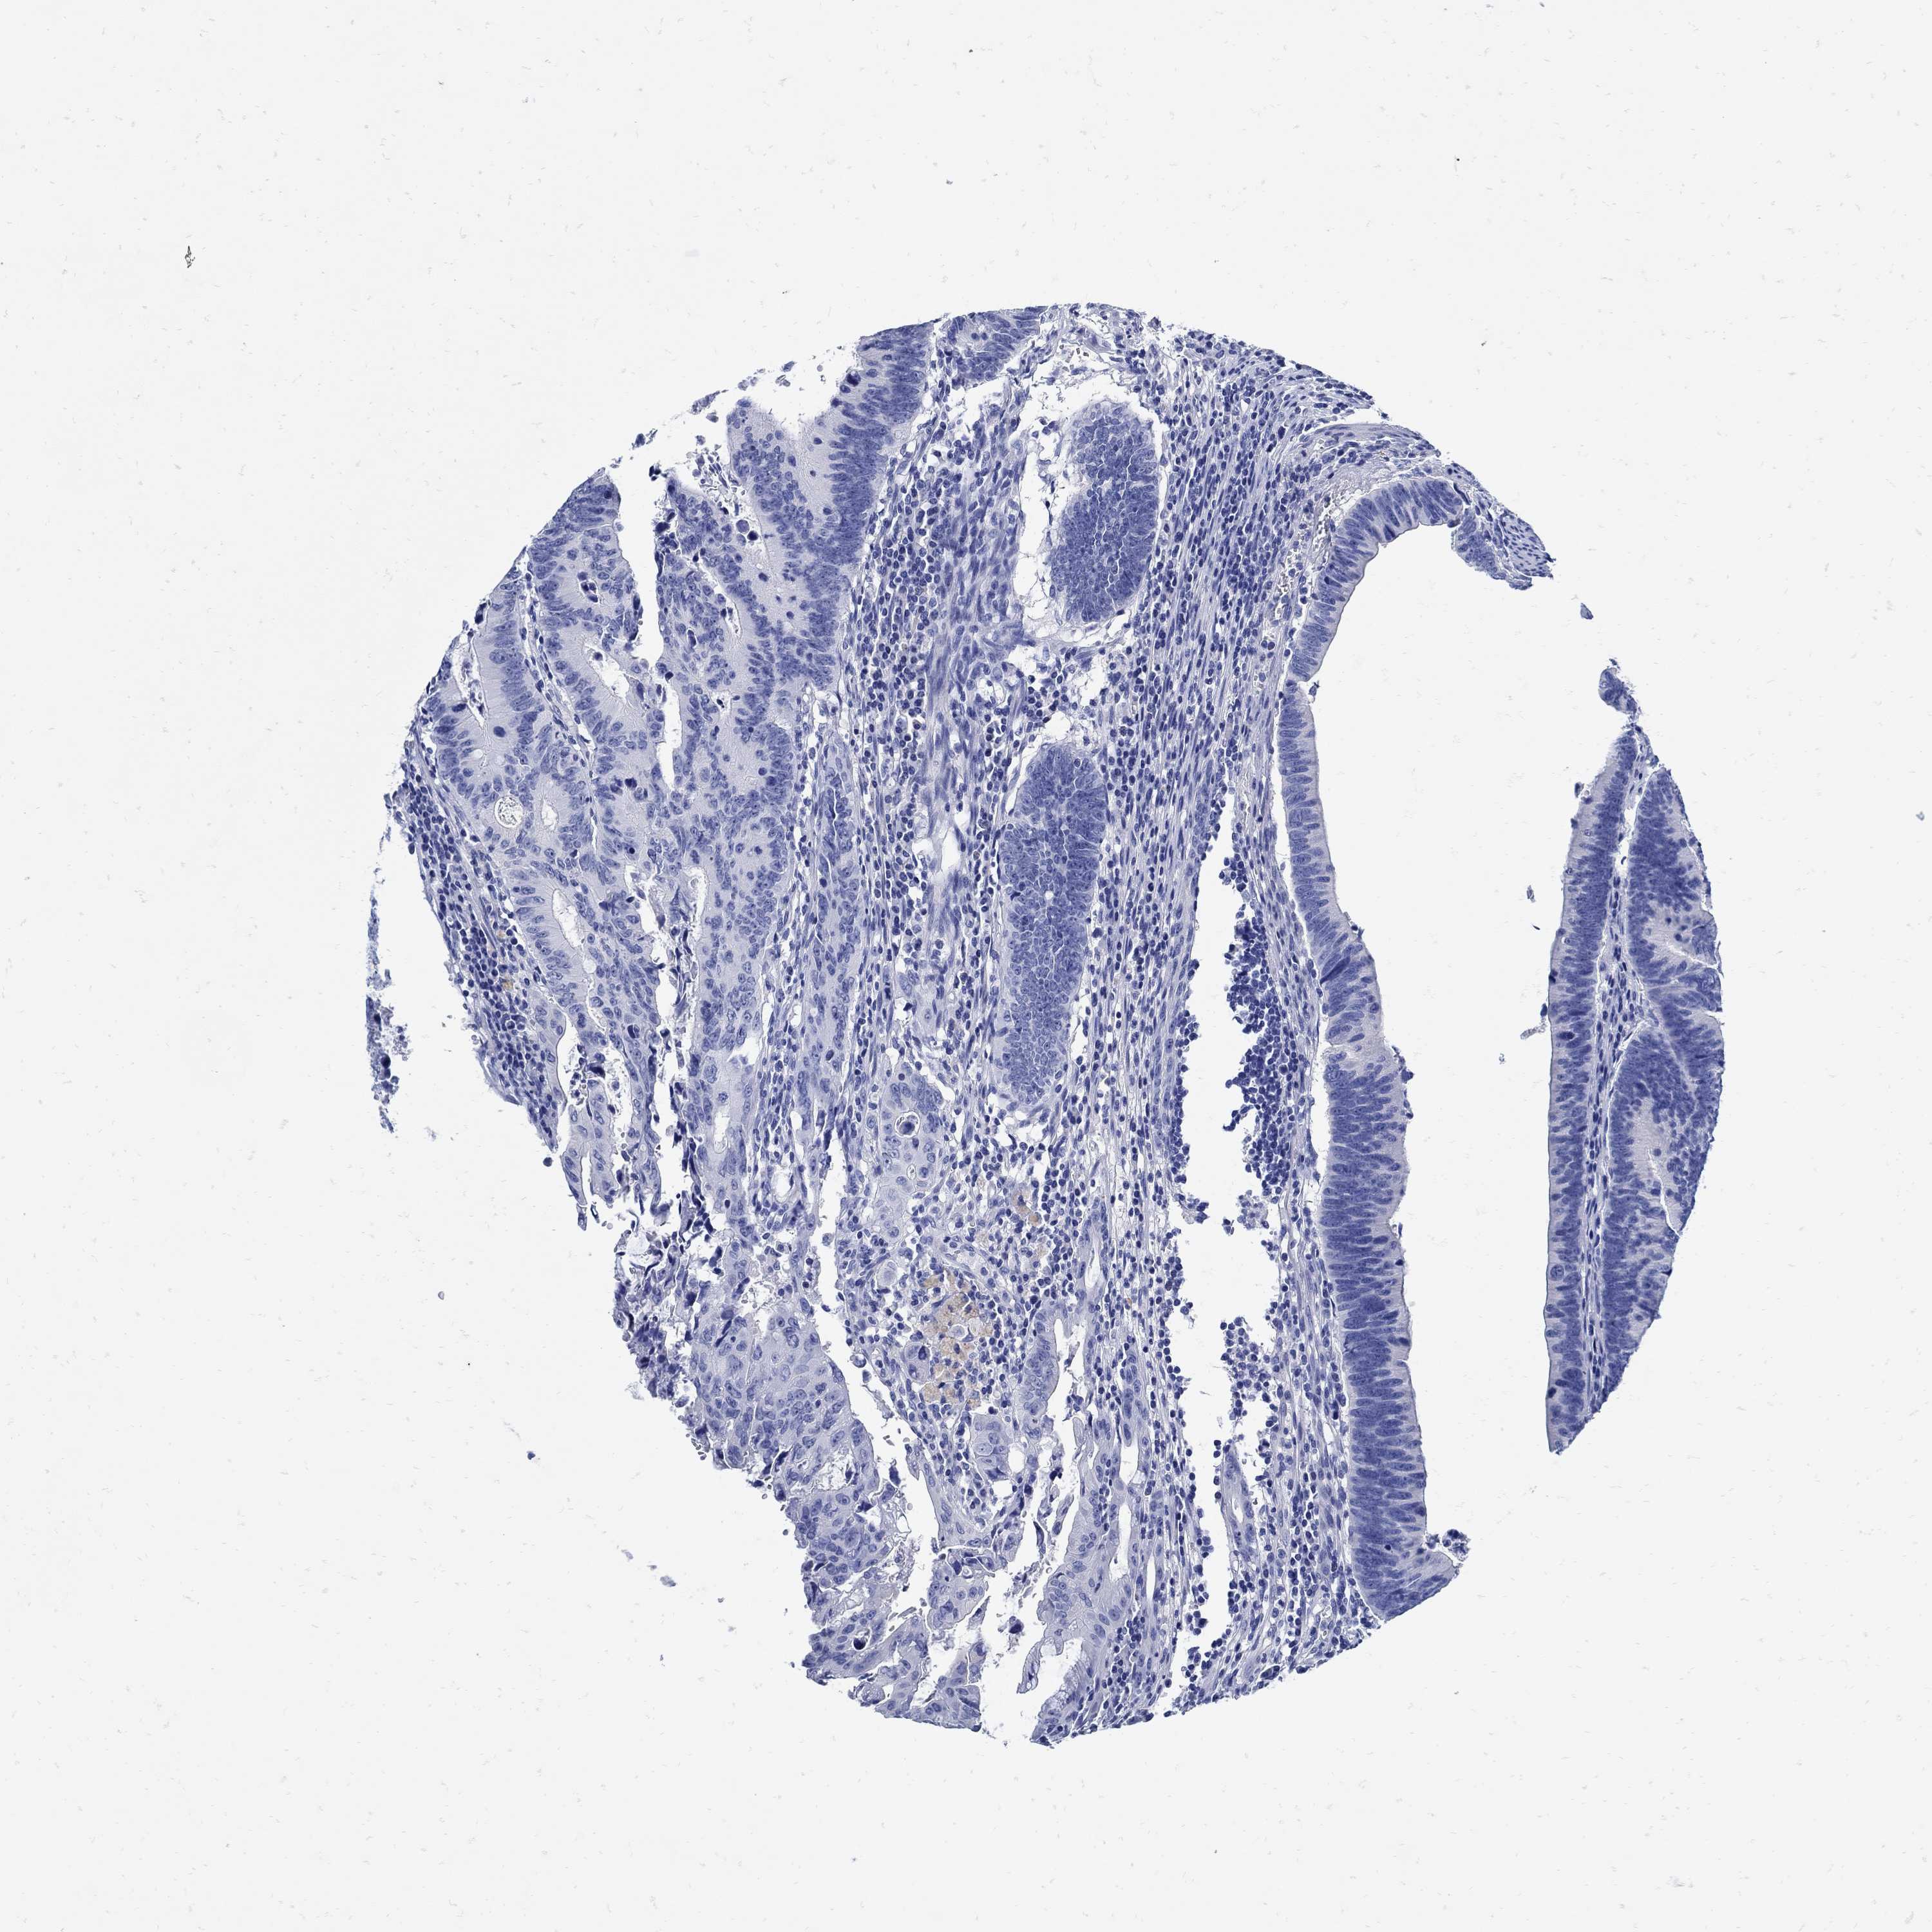

Colorectal cancer

Rectum adenocarcinoma